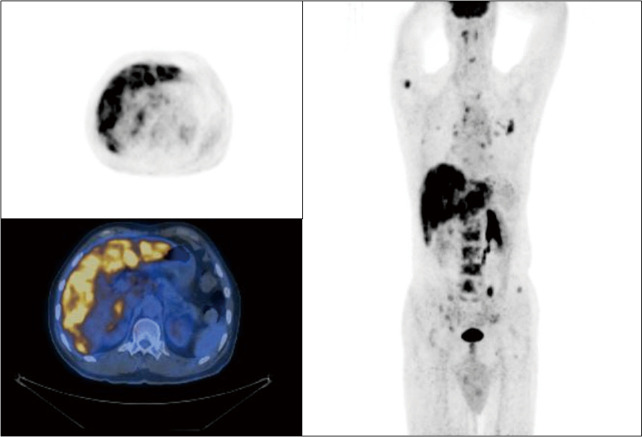

Case description: Here, we reported the genetic results of a patient with a PIK3CA gene mutation in scrotal Paget's disease who developed multiple metastases to the lymph nodes, liver, and bones during adjuvant radiotherapy, as well as the results of treatment with a PIK3CA inhibitor. The latest advances in this field were also summarized. The treatment response was evaluated as stable disease (SD) after 6 courses of docetaxel plus tegafur (DS regimen) chemotherapy. Then, a second-line treatment, a PIK3CA inhibitor, WX390, was administered with tolerable toxicity. There was a treatment-induced increase in blood glucose level during treatment, and insulin was administrated with good control. The progression-free survival (PFS) was 3.9 months and the overall survival (OS) was 16 months.